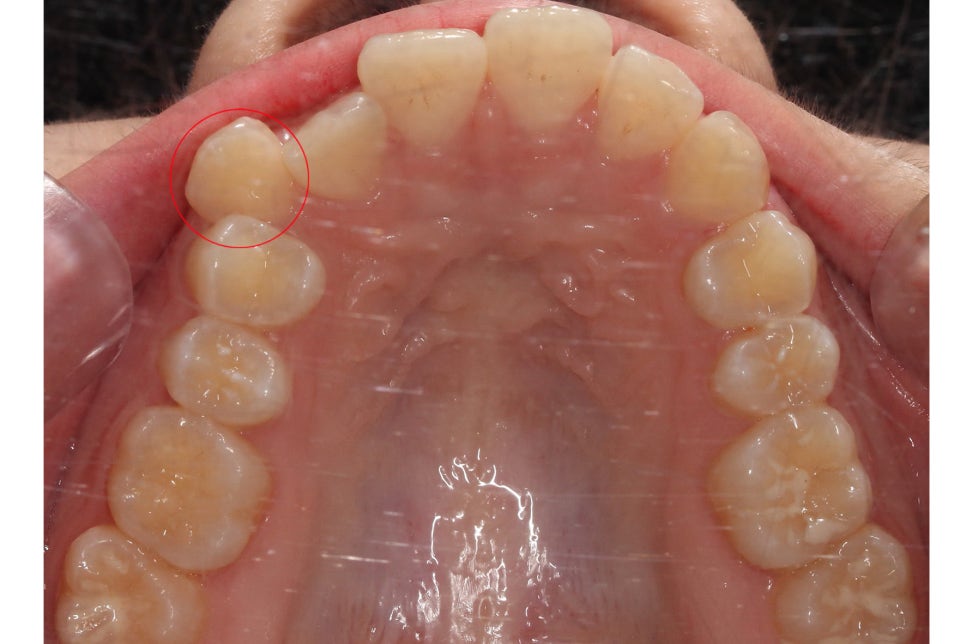

송곳니덧니 교정 전 상악의 치아 배열을 보면

전체적으로 좁고 긴 안모의 모습을 하고 있는데요,

순측으로 뻐드러져 있는 견치를 바른 각도로

조정하기 위해서 구치부 치아를 이동시켜

공간을 확보해야 할 것으로 보입니다.